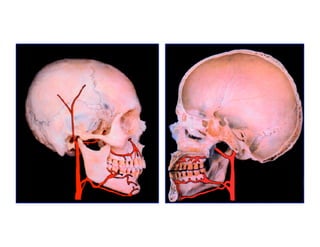

Este documento describe los principios de construcción de la arquitectura craneofacial, incluyendo el metamerismo, la simetría y la paquimería. Explica la organización peri-cavitaria del cráneo a través de columnas y vigas, y analiza las diferentes fascias profundas del cuello. También destaca la importancia de conocer la irrigación ósea con orientación quirúrgica, mencionando los principales aportes vasculares y suplementarios así como el origen, trayecto y retorno venoso de la carót